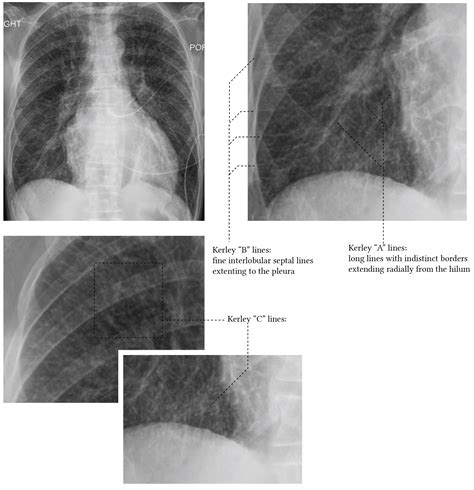

Kerley B Lines

In the field of diagnostic radiology, recognizing specific patterns on a chest X-ray is vital for timely medical intervention. Among the most recognizable and clinically significant findings are Kerley B lines. These thin, short, horizontal lines are frequently identified at the lung periphery and serve as a hallmark indicator of interstitial pulmonary edema. Understanding what these lines signify and how to identify them is essential for healthcare professionals and students alike, as they often provide the first visual clue that a patient is experiencing significant fluid overload, commonly associated with conditions like congestive heart failure.

Kerley B lines are radiographic markers that represent thickened interlobular septa. In a healthy lung, these septa are extremely thin and typically invisible on standard posterior-anterior (PA) chest radiographs. However, when fluid accumulates within these spaces—a condition known as interstitial edema—the septa swell, making them dense enough to be visualized as distinct linear opacities.

These lines are distinct because of their specific orientation and location:

• Appearance: They appear as fine, horizontal, unbranching lines.

• Location: They are found primarily at the lung bases, perpendicular to the pleura.

• Length: They are short, usually measuring less than 2 centimeters in length.